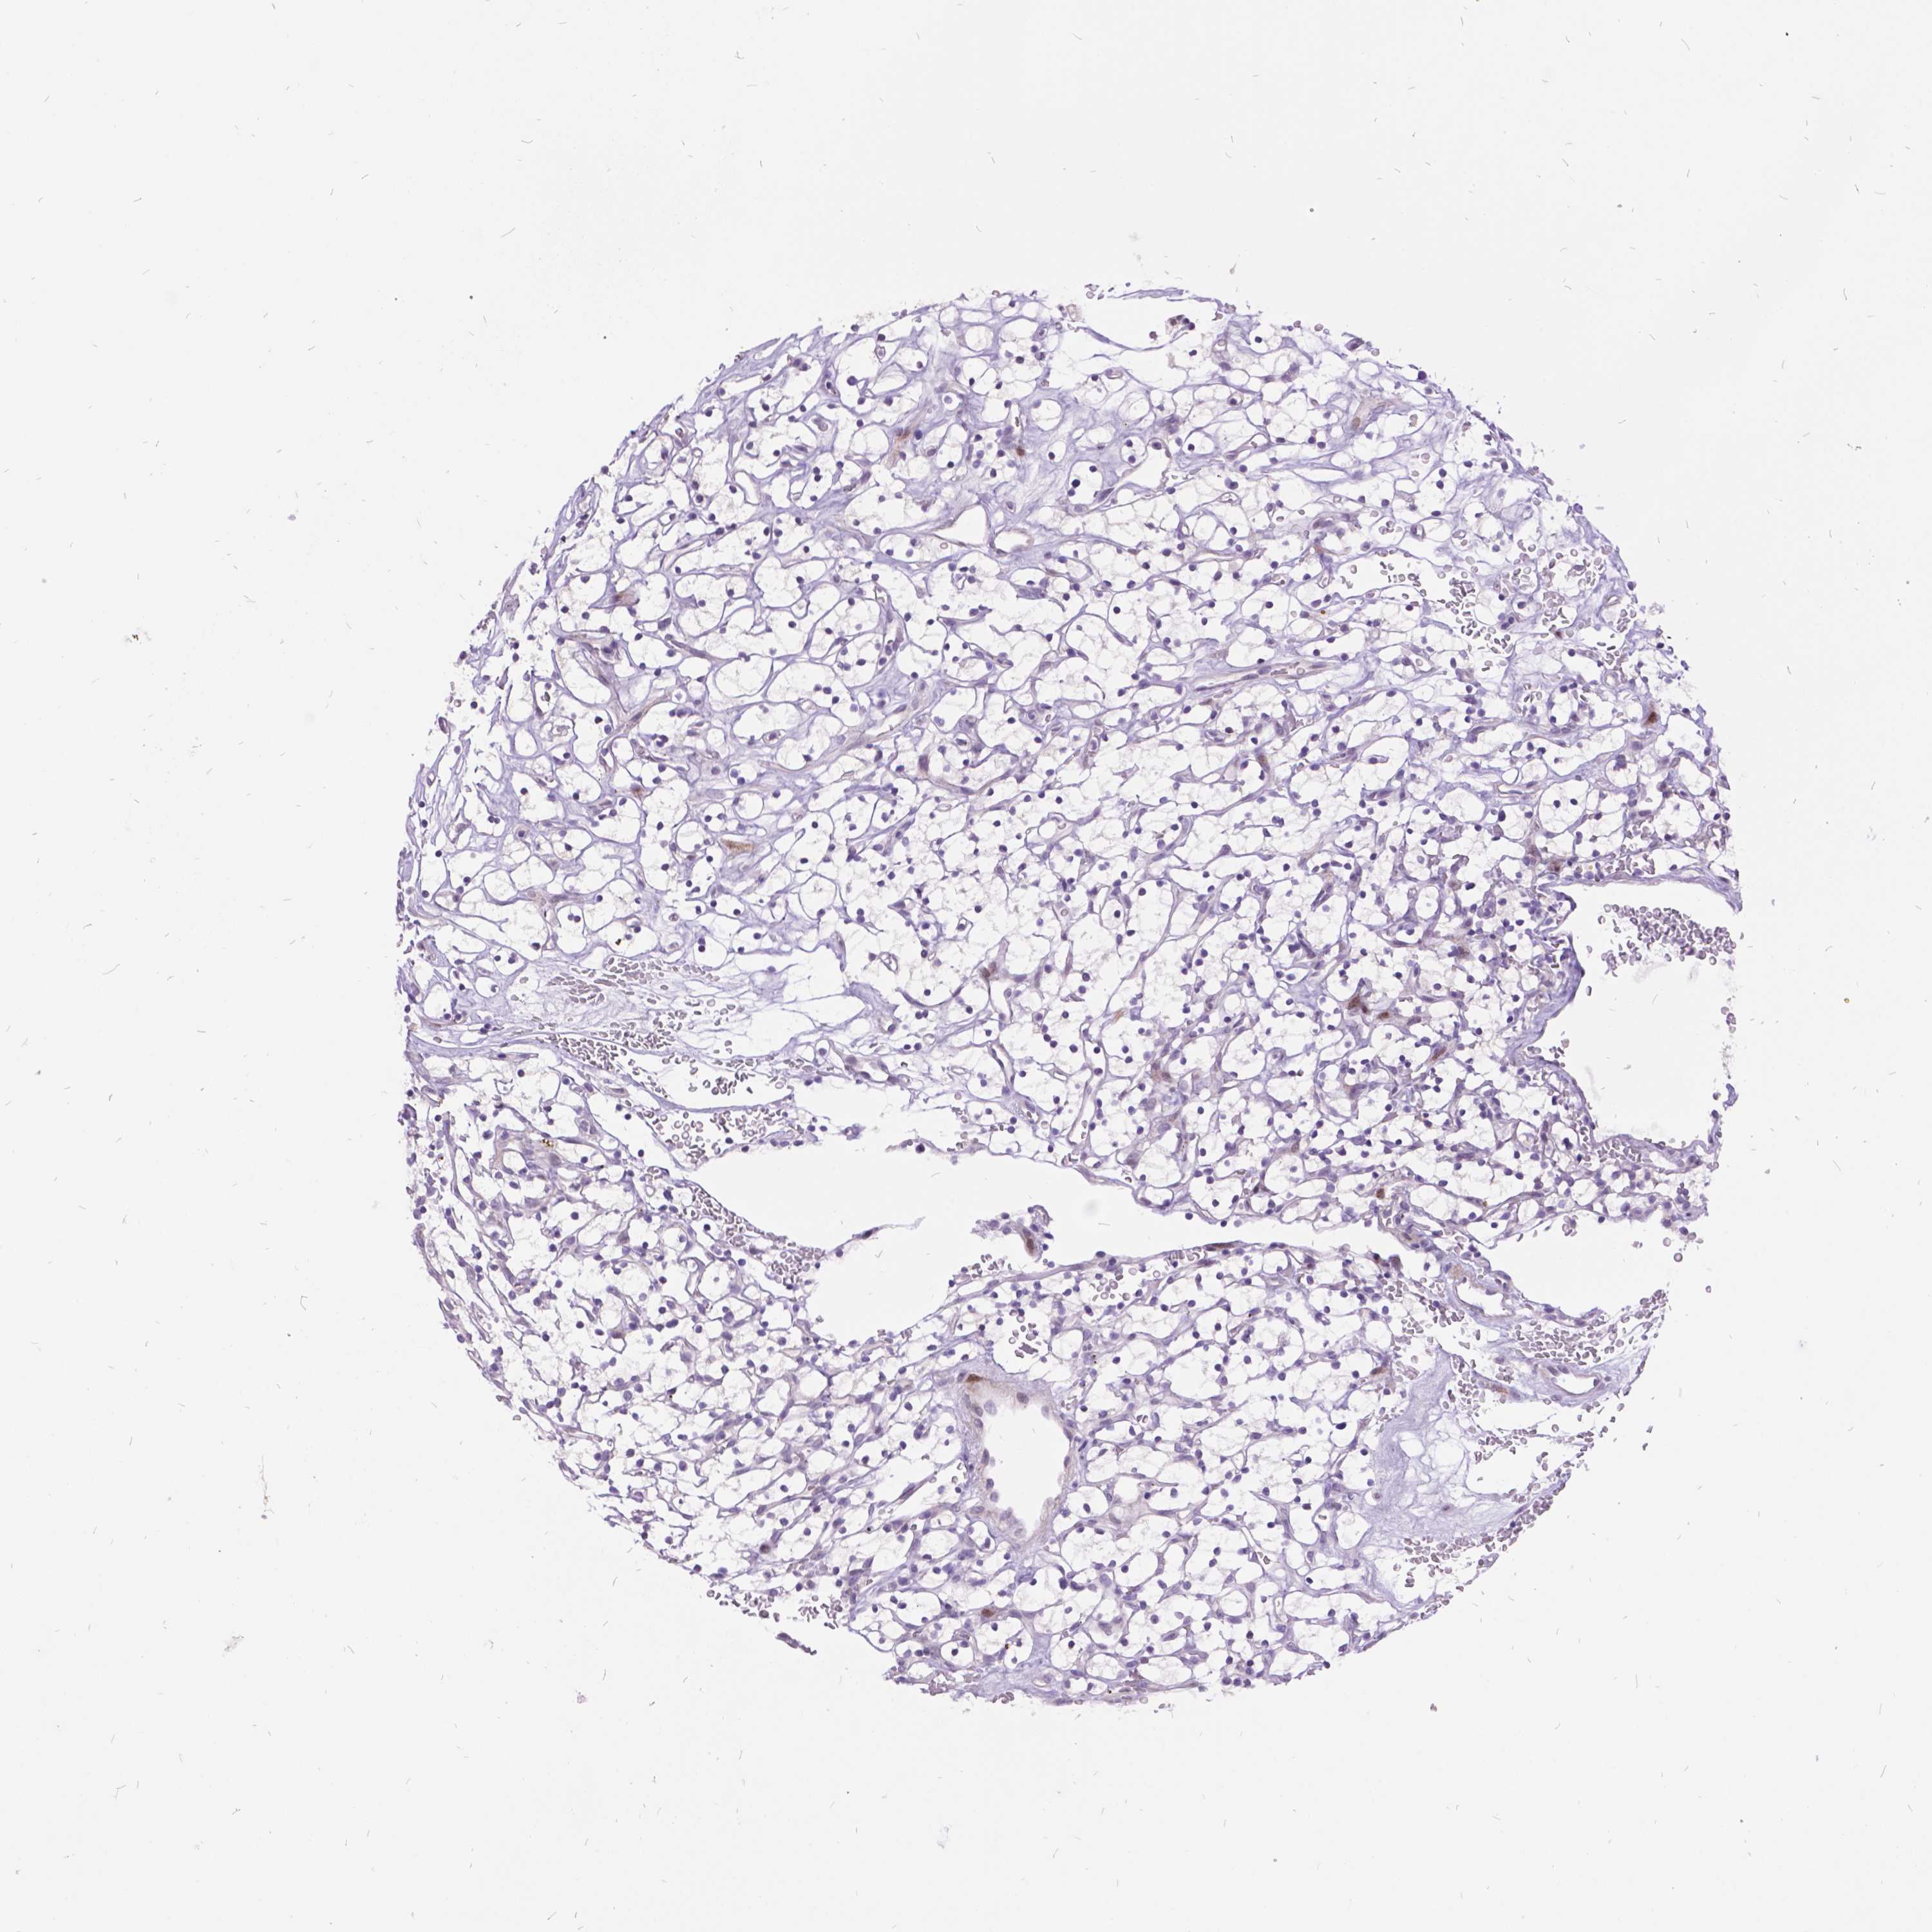

KIDNEY RENAL CLEAR CELL CARCINOMA (VALIDATION) - Interactive survival scatter ploti

The Survival Scatter plot shows the clinical status (i.e. dead or alive) for all individuals in the patient cohort, based on the same data that underlies the corresponding Kaplan-Meier plots. Patients that are alive at last time for follow-up are shown in blue and patients who have died during the study are shown in red.

The x-axis shows the expression levels (FPKM) of the investigated gene in the tumor tissue at the time of diagnosis. The y-axis shows the follow-up time after diagnosis (years). Both axes are complimented with kernel density curves demonstrating the data density over the axes. The top density plot shows the expression levels (FPKM) distribution among dead (red) and alive patients (blue). The right density plot shows the data density of the survived years of dead patients with high and low expression levels respectively, stratified using the cutoff indicated by the vertical dashed line through the Survival Scatter plot. This cutoff is automatically defined based on the FPKM cutoff that minimizes the p-score. The cutoff can be changed by dragging the vertical line or by entering a cutoff value in the square labeled "Current cut-off".

Under the Survival Scatter plot the p-score landscape (black curve; left axis) is shown together with dead median separation (red curve; right axis). Dead median separation is the difference in median mRNA expression between patients who have died with high and low expression, respectively. It is calculated as follows: median FPKM expression of dead patients with high expression - median FPKM expression of dead patients with low expression. This is intended to aid the user in visually exploring custom cutoffs and the associated p-scores and dead median separation.

Individual patient data is displayed and can be filtered by clicking on one or more of the category buttons on the top of the page. Categories describing expression level and patient information include: high, low, alive, dead, female, male and tumor stages. The scale of the x-axis can be toggled between linear and log-scale by clicking on the "x log" button. Mouse-over function shows TCGA ID, patient information and mRNA expression (FPKM) for each patient.

& Survival analysisi

Kaplan-Meier plots summarize results from analysis of correlation between mRNA expression level and patient survival. Patients were divided based on level of expression into one of the two groups "low" (under cut off) or "high" (over cut off). X-axis shows time for survival (years) and y-axis shows the probability of survival, where 1.0 corresponds to 100 percent.

ITGB6 is not prognostic in Kidney Renal Clear Cell Carcinoma (validation)

Best expression cut offi

: 10.82

P scorei

N/A

Average pTPM 8.4

Number of samples 100